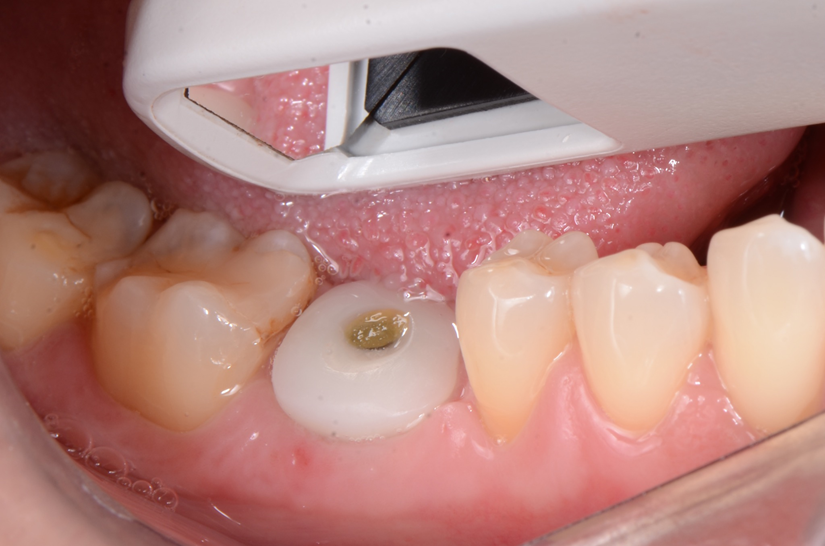

O paciente apresentou fratura vertical mésio-distal no elemento 46. Foi planejada a exodontia minimamente traumática e instalação imediata do implante Maestro Superiore (Implacil Osstem) utilizando uma guia prototipada. Após a exodontia, o implante foi instalado seguindo o protocolo de cirurgia guiada. O GAP vestibular foi preenchido com o Extra Graft. Um cicatrizador personalizado impresso com haletas facilitadoras foi capturado com resina flow e instalado. Após 30 dias, foi realizado escaneamento indireto para obtenção do perfil de emergência, utilizando protocolo digital com sobreposição do cicatrizador escaneado para confecção da coroa definitiva em zircônia policristalina estabilizada por ítria.

O uso de cicatrizadores personalizados, especialmente confeccionados por impressão 3D, tem ganhado destaque por permitir a conformação tecidual progressiva, facilitando a reprodução do perfil de emergência no fluxo digital6,7. A captura do cicatrizador com haletas de retenção com resina flow e seu posterior escaneamento são etapas críticas para assegurar a fidelidade da transferência do perfil de emergência e garantir um planejamento restaurador mais previsível8.

Neste caso, a sobreposição digital entre o cicatrizador escaneado e o desenho da coroa possibilitou comparar perfis de emergência com excelente adaptação clínica, contribuindo para um resultado estético e funcional adequado.